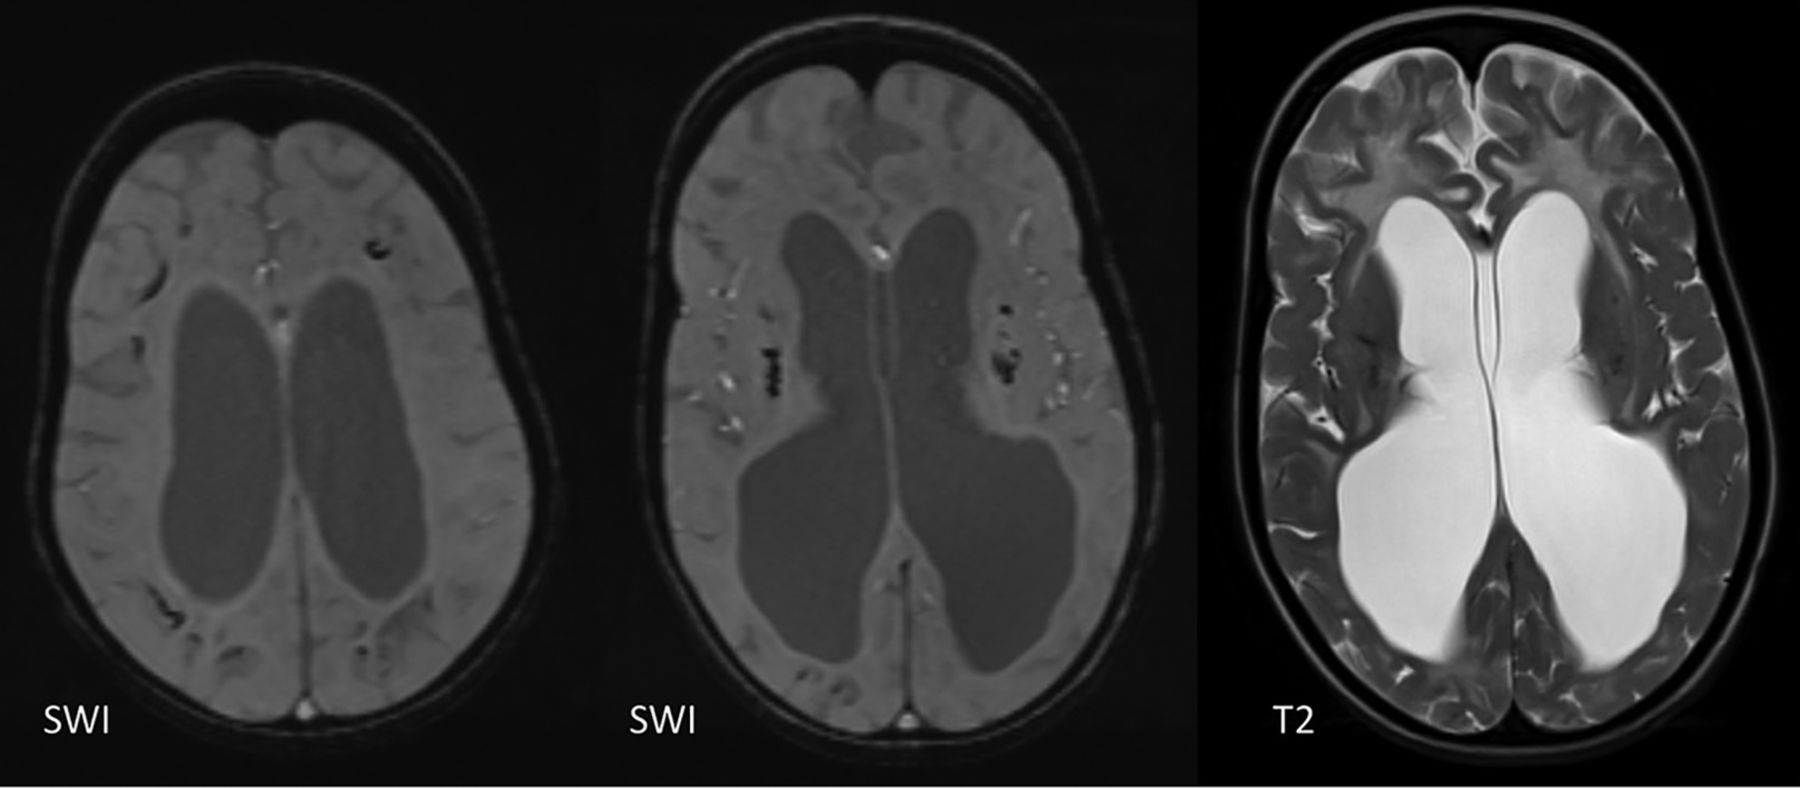

Some leukodystrophies, like Cockayne syndrome, can have a very similar appearance with diffuse WMH and ICC. Unlike AGS, there is a severe delay or an arrest in myelination, and the calcifications can be cortical/leptomeningeal (Fig 14).42

A 6-year-old boy with Cockayne syndrome showing subcortical and basal ganglia calcifications on SWI and diffuse WM signal abnormality seen on the T2-weighted image. There is marked WM volume loss.